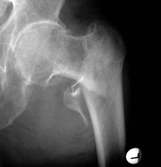

Seitlich wurde der Nagel fehlpositioniert, was

beim Belasten zum Auswandern führte. Mit dem Zielgerät

nach Asche wäre dies nicht passiert.